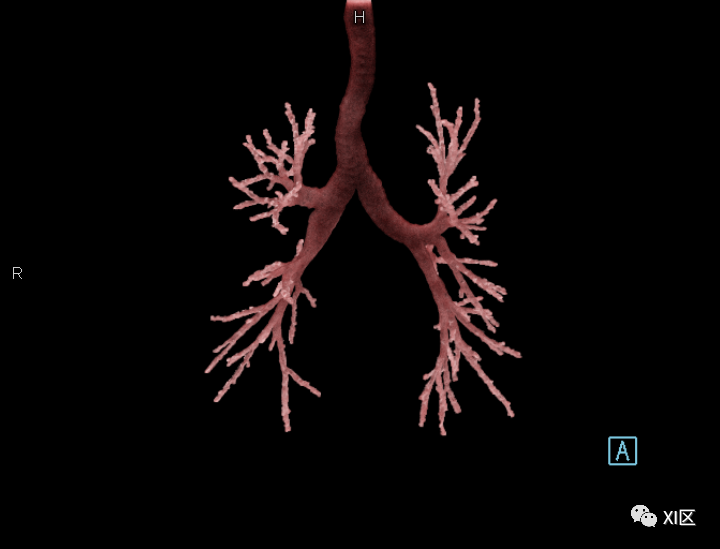

第二,

我们仔细观察了牛蛙的肺结构

不同于人类

牛蛙的两肺气管很粗大

直接和声门相连

气出来的更顺利

肺与气管、声门的位置关系

作为对比,人类的气道要更细更狭长 SOMATOM Force扫描 cVRT重建

牛蛙肺部细节

肺部血管分布